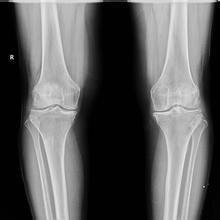

(图:治疗前膝关节红肿异常)

(图:经治疗后李先生双膝关节已与常人无异)